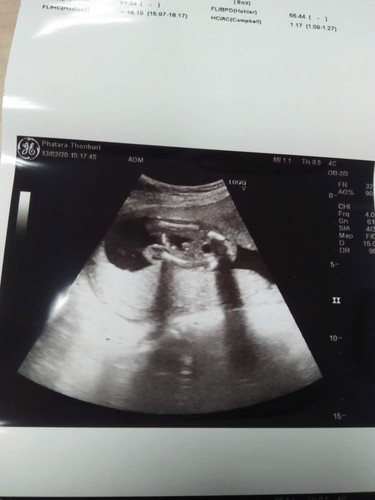

อยากรู้จังว่าชาย/หญิง คุณหมอถ่ายมาแบบนี้ค่ะ

ชายค่ะ